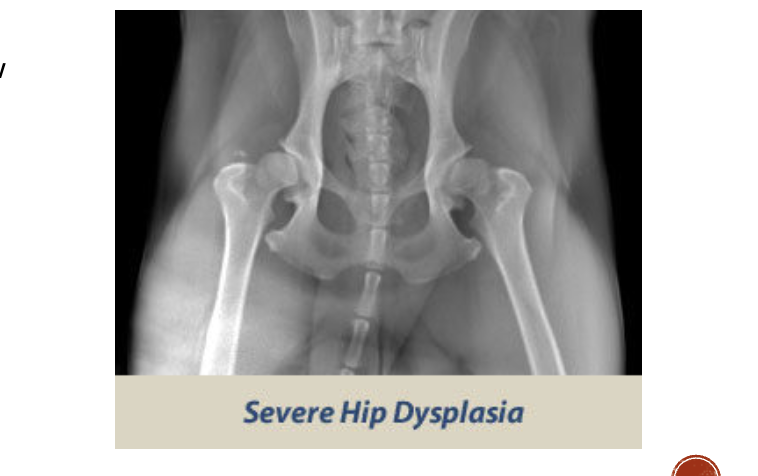

OFA severe dysplasia

Marked evidence

Ball partly/ completly out of shallow socket

significant arthritc bone changes

What are some signs of arthritic changes

Acetabulum is almost not visible

Bone spurs above hip joints

Thickening and remodeling of the femoral head